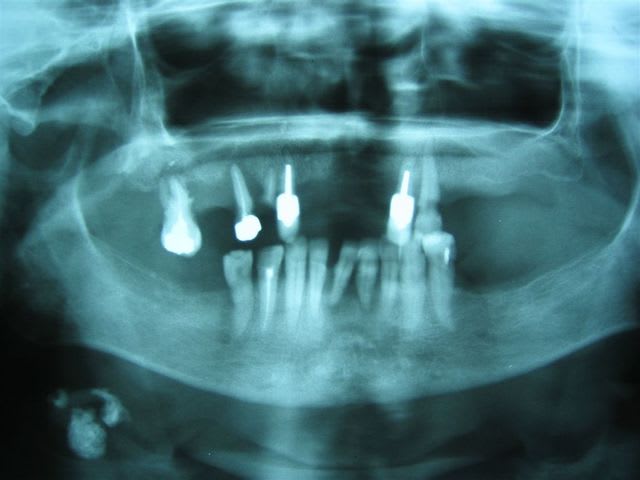

16/09/2006 à 11h42

... comptez

Nl 1 ar0gah - Eugenol

... comptez ... les cônes d'argent!

W - Eugenol

... patiente née en 1946, endos datant d'une quarantaine d'années ... et pas de foyer ... la nature est bonne :)

Par contre pour sortir ces m*rdes, c'est la galère, ça casse très facilement.

Ta deuxième photo fait penser aux implants transfixiants de Samy Sandhaus... La preuve que ça marche...